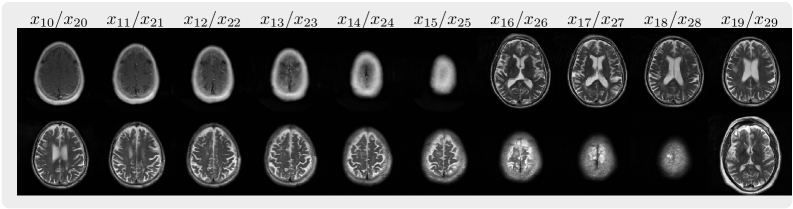

| FastMRI 2D multi-slices | Cardiac Cine | ABIDE 3D volume |

download_pretrained: Downloads pretrained models and sample data necessary for reconstruction and sampling.unfolding: Performs MRI unfolding using pretrained models to generate high-resolution images usingsample.py.reconstruction: Conducts volume reconstruction of MRI images using pretrained models usingfastmri_recon.py.sampling_brain: Generates sample MRI images using pretrained models usingsample.py.sampling_cardiac: Generates sample cardiac cine images using pretrained models usingsample.py.